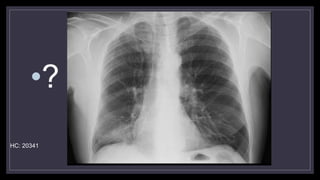

•?

HC: 20341